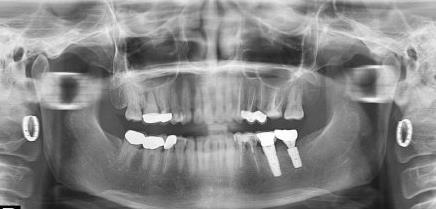

後牙種植牙

還有,烤瓷牙壞了,能不能種牙其實還要看牙周情況,牙槽骨情況。如果全口牙周條件好,牙槽骨骨量充足,通常則不用擔心什麽(me) 問題。但是如果有嚴(yan) 重牙周病,而且牙槽骨萎縮嚴(yan) 重,則可能需要麵臨(lin) 牙周治療、植骨等重重的考驗之後才能確定是否達到種植牙的標準。